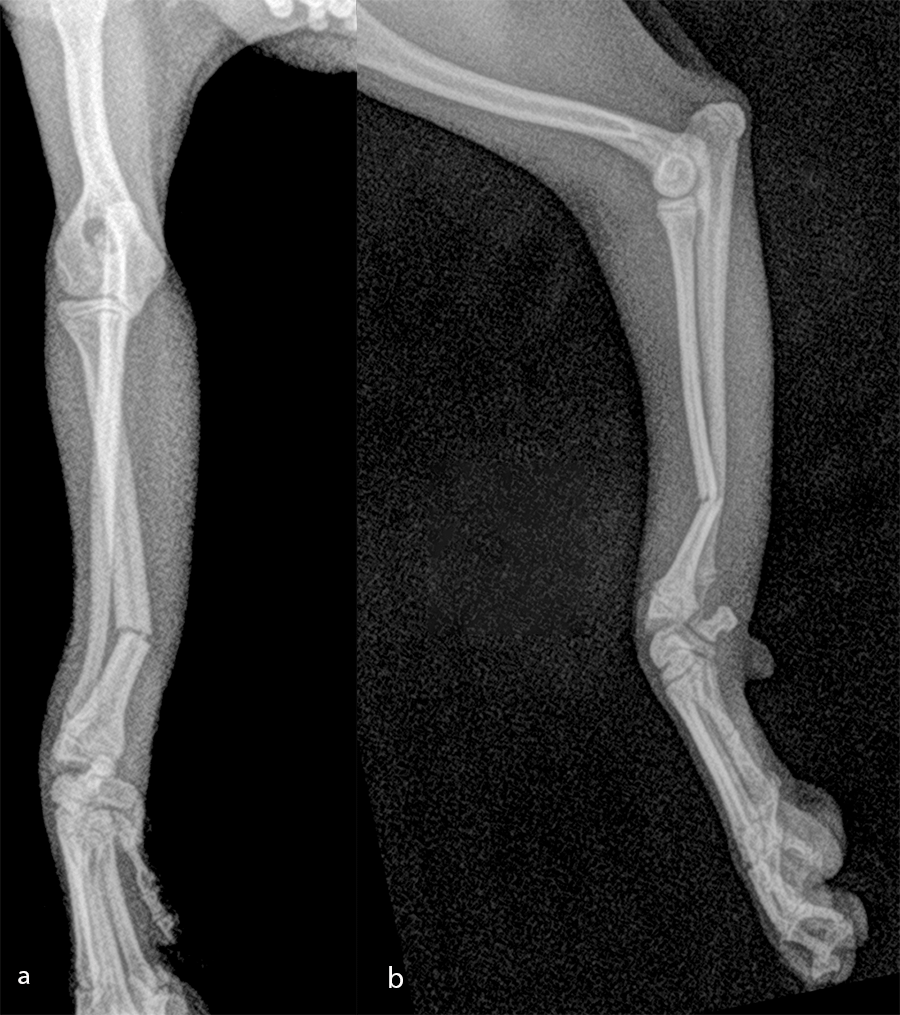

Open reduction and internal fixation of distal radial and ulna fractures with a single 1.3 radial plate (Fig 6).

The patient was a 6-month-old, 1 kg (exactly 0.950 kg) Pomeranian dog presenting with a radial fracture of the left thoracic limb after a jump from ≈ 50 cm. The 1.5 mm System was too large for the width of the radius (2.2 mm) and the width of the radial medullary canal (0.5 mm) (Fig 7). The 1.3 mm adaptation plate was a perfect plate for this fracture. This plate option permitted the use of cortex and locking screws.